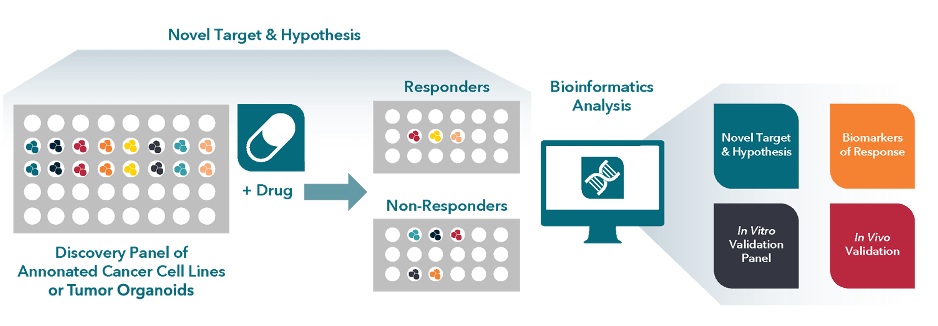

In vitro screening offers a high-throughput, cost-effective platform for early biomarker discovery and refinement, helping identify drug leads, targets, mechanisms of action (MoA), and genetic markers associated with drug response, and guide future in vivo model selection.

Our 2D cell lines and 3D tumor organoids provide rapid, data-driven insights, helping optimize early-stage research decisions.

Fig. Example workflow of in vitro compound screening

Fig. Example workflow of in vitro compound screening